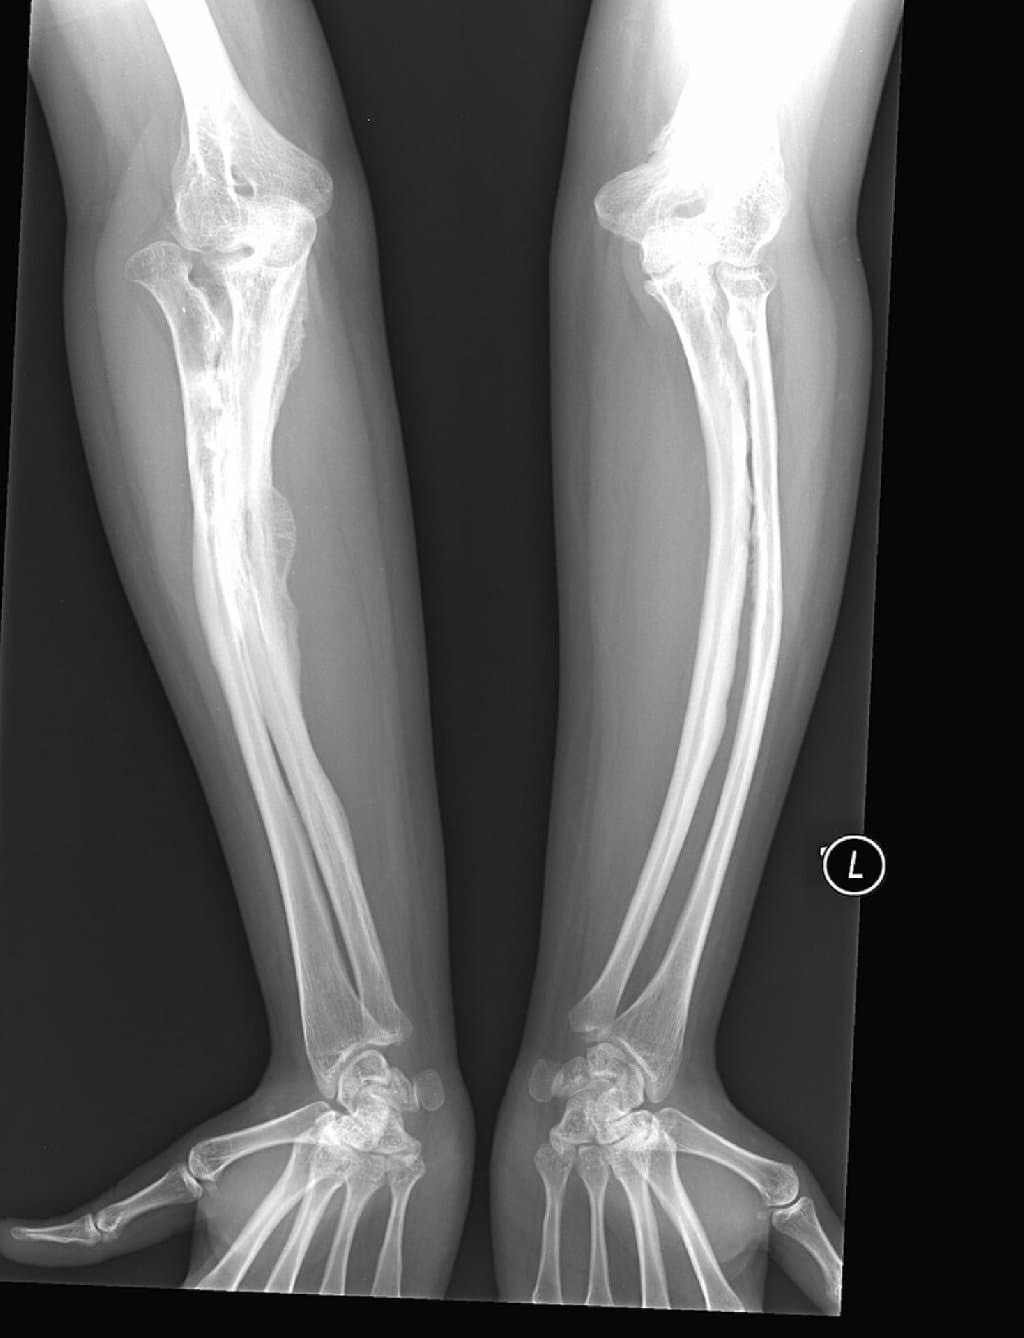

Bu xəstəliyin ən xarakterik simptomu oynaqlarda müşahidə olunan şiddətli ağrı və inflamasiya (iltihab) prosesidir. Ağrılar xüsusilə gecə saatlarında kəskinləşir və bəzən o qədər dözülməz olur ki, xəstə zədələnmiş nahiyəyə toxunulmasına belə icazə verə bilmir. Xəstəlikdən ən çox təsirlənən nahiyələr aşağıdakılardır:

- Diz oynaqları

- Əl oynaqları